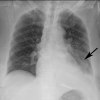

The coronavirus disease 2019 (COVID-19) pandemic is a global health care emergency. Although reverse-transcription polymerase chain reaction testing is the reference standard method to identify patients with COVID-19 infection, chest radiography and CT play a vital role in the detection and management of these patients. Prediction models for COVID-19 imaging are rapidly being developed to support medical decision making. However, inadequate availability of a diverse annotated data set has limited the performance and generalizability of existing models. To address this unmet need, the RSNA and Society of Thoracic Radiology collaborated to develop the RSNA International COVID-19 Open Radiology Database (RICORD). This database is the first multi-institutional, multinational, expert-annotated COVID-19 imaging data set. It is made freely available to the machine learning community as a research and educational resource for COVID-19 chest imaging. Pixel-level volumetric segmentation with clinical annotations was performed by thoracic radiology subspecialists for all COVID-19-positive thoracic CT scans. The labeling schema was coordinated with other international consensus panels and COVID-19 data annotation efforts, the European Society of Medical Imaging Informatics, the American College of Radiology, and the American Association of Physicists in Medicine. Study-level COVID-19 classification labels for chest radiographs were annotated by three radiologists, with majority vote adjudication by board-certified radiologists. RICORD consists of 240 thoracic CT scans and 1000 chest radiographs contributed from four international sites. It is anticipated that RICORD will ideally lead to prediction models that can demonstrate sustained performance across populations and health care systems.